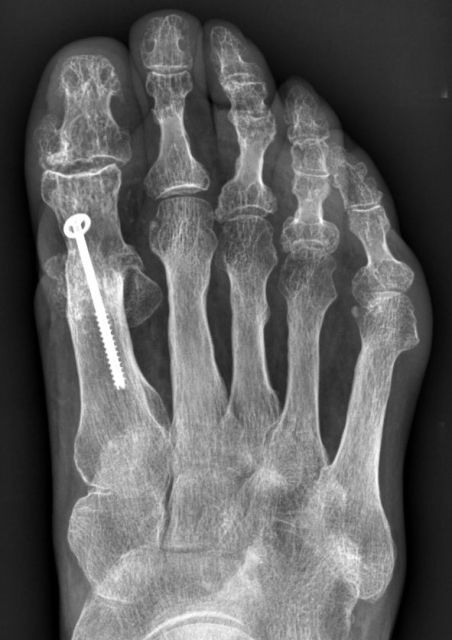

Großzehengrundgelenksversteifung (Großzehengrundgelenksarthrodese)